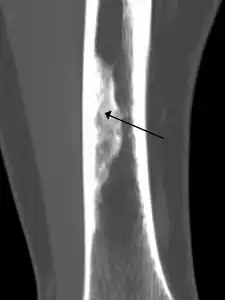

2. An ossified non-ossifying fibroma on CT